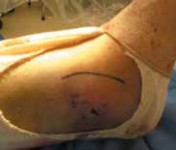

DIRECT LATERAL APPROACH TO THE FIBULA Exposure

The incision is kept just off the posterior border of the fibula but may be adjusted slightly based on soft tissue considerations (

TECH FIG 1A

).

A B C TECH FIG 1•

Surgical approach to the fibula, direct lateral.

A.

Skin incision marked out just along the posterior border of the fibula, centered about the level of the fracture.

B.

Incision through the peroneal (lateral compartment) fascia, exposing the fracture site.

C.

Identification of the superficial peroneal nerve as it crosses proximally in the wound.